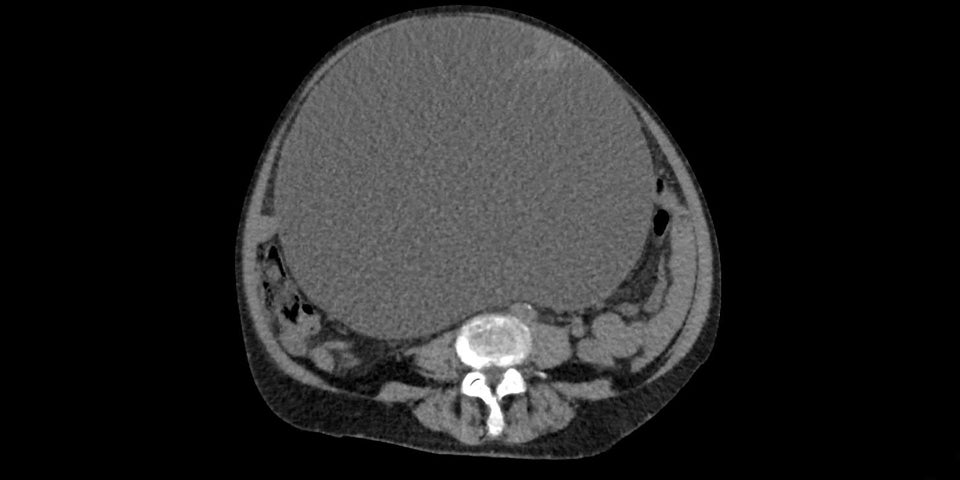

Klagenfurt. Ärzte des Klinikums Klagenfurt haben einen zehn Kilogramm schweren Tumor aus dem Bauch einer 73-jährigen Patientin entfernt. Wie der Krankenanstaltenbetreiber Kabeg am Donnerstag in einer Aussendung mitteilte, hatte die Frau wegen einer vermeintlichen Wasseransammlung in ihrem Bauch ihren Hausarzt konsultiert. Die Operation verlief erfolgreich - bereits fünf Tage nach der Operation konnte die 73-Jährige das Krankenhaus verlassen.

Die Diagnose im Klinikum Klagenfurt lautete auf Eierstockkrebs im Frühstadium. Die Entfernung des 10,2 Kilogramm schweren und im Durchmesser 30 Zentimeter großen Tumors verlief ohne Probleme: "Die Patientin benötigt weder eine Chemotherapie noch eine Strahlentherapie", erklärte Reinhard Mittermair, der Abteilungsvorstand der Allgemein- und Viszeralchirurgie am Klinikum Klagenfurt.